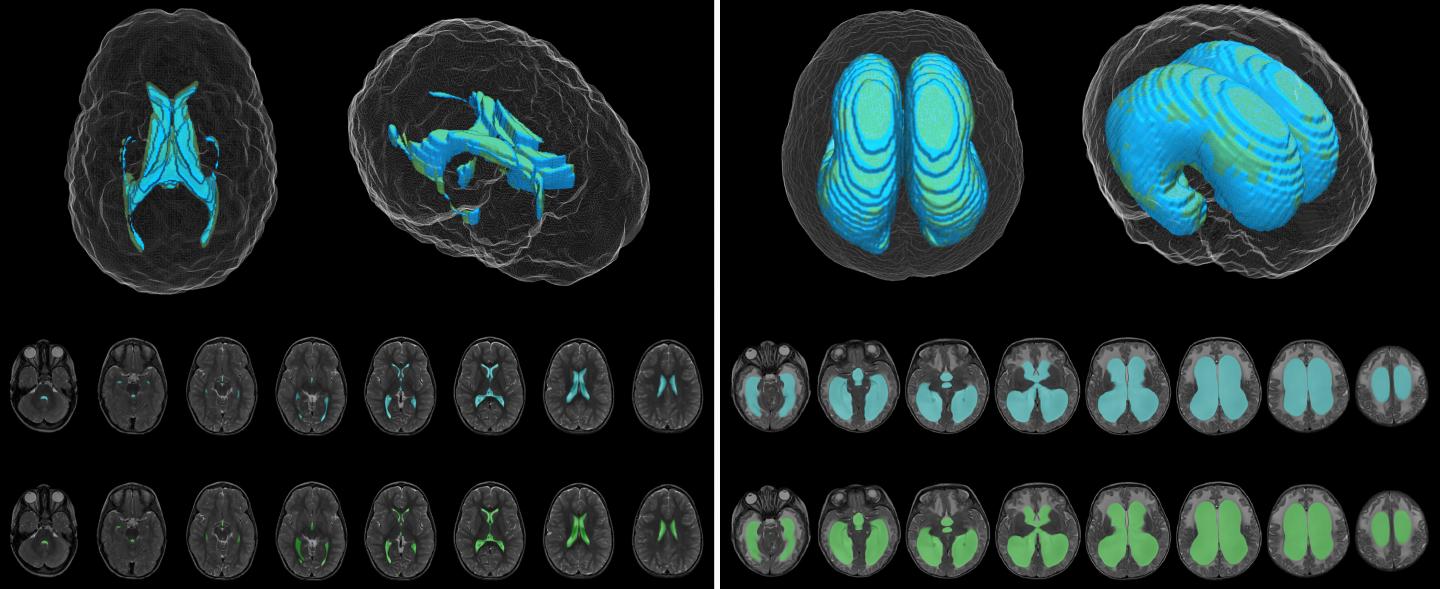

image: Deep learning model (blue) and ground truth manual (green) segmentation of representative control (left) and hydrocephalus (right) T2-weighted MR images.

The DL model was designed to produce automatic ventricle segmentation (delineation of ventricle borders on imaging) and volume calculation. To examine the efficiency of the model, the authors compared these two processes to the gold standard of manual segmentation and volume calculation and to the use of FreeSurfer research software. The authors used the Dice similarity coefficient (0 to 1) to assess segmentation accuracy and linear regression to assess volume calculation.

According to the authors, when compared to manual segmentation, "model segmentation performed with an overall Dice score of 0.901 (0.946 in hydrocephalus, 0.856 in controls)." These numbers show great accuracy, with even better accuracy evident when used in patients with hydrocephalus. When used to assess segmentation accuracy in the patients at Utah Primary Children's Hospital, the Dice score was 0.926.